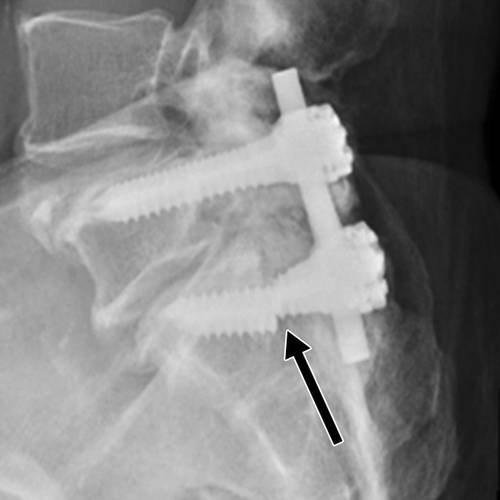

图1 -57岁的男子L5-S1融合。 侧位片显示螺钉(箭头)刺穿S1椎体皮层,触及直肠后壁,有造成肠道破裂的风险。